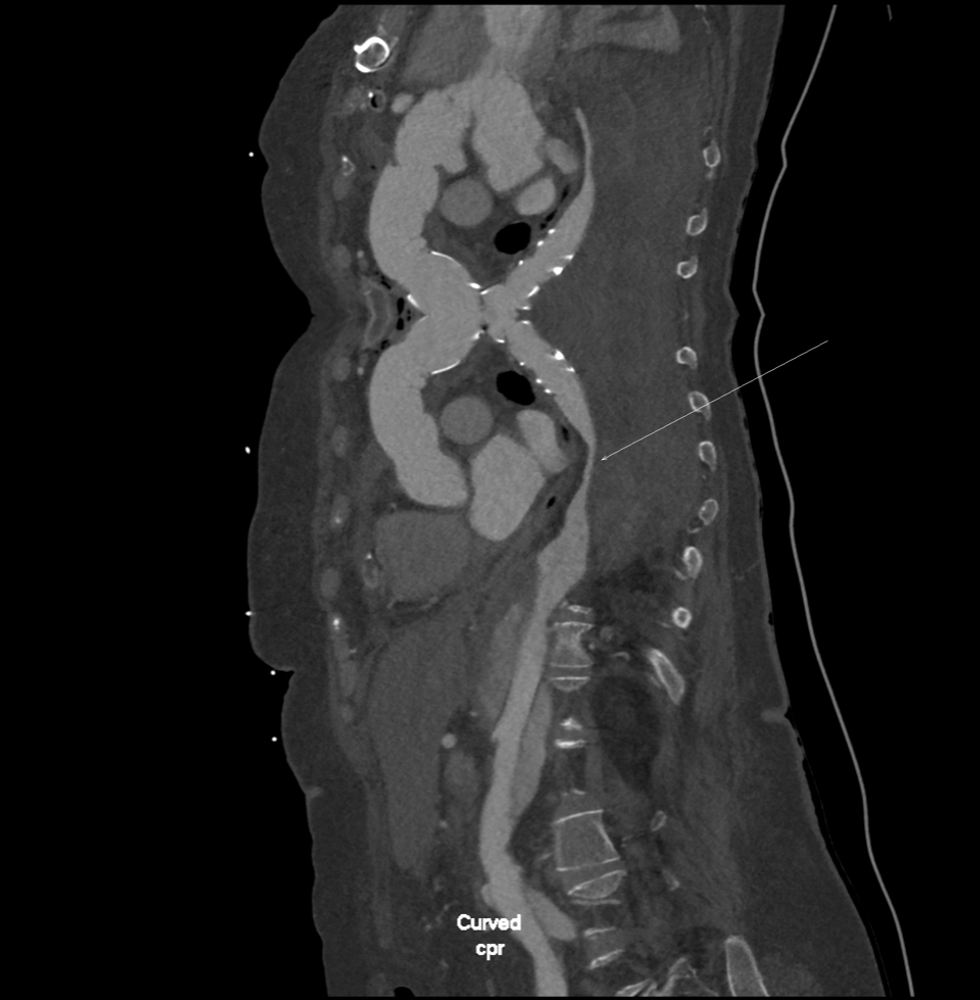

Doktor Zhan Mitrev së bashku me ekipin e tij kryen me sukses një operacion kompleks hibrid FET (Frozen Elephant trunk). Ky operacion paraqet zgjidhje për gjendjen komplekse të rupturës (diseksionit) të aortës, gjatë së cilës vendoset një protezë e posaçme e aortës në harkun dhe në pjesën zbritëse të aortës.

Operacioni i është kryer tek pacientja 66-vjeçare në gjendje kërcënuese për jetën me një problem kronik – aneurizëm që ka çuar në kolaps mushkërinë e majtë dhe ka shkaktuar probleme me frymëmarrjen. Ky nuk është operacioni i parë për të. Më parë pacientja i është nënshtruar një operacioni urgjent për zëvendësimin e rrënjës së aortës për shkak të disekcionit akut Stanford A (DeBakey tip 1), me qëllim riparimin e plasaritjes (diseksionit) të aortës në atë moment dhe shpëtimin e jetës së pacientes.